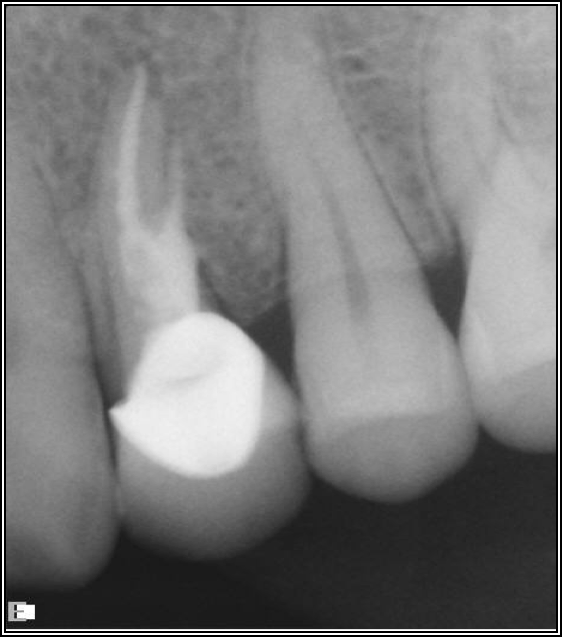

As to which material to use, the literature indicates fiber is better because it has greater flexibility and is less likely to allow for vertical fractures.2,3 It also has better esthetics, which is significant for both anterior and posterior teeth. The problem with fiber posts is that they can snap off and pull out. When they snap off, they are difficult to remove. A tapered diamond bur or ultrasonic can be used, but it must be done very carefully. Depending on the circumstances, metal can also be difficult, but metal is often serrated or threaded and can be unwound with an ultrasonic. However, fiber is significantly more flexible because it has a better modulus of elasticity, which should be as close to the dentin's elasticity as possible. On the radiograph, it can be difficult to see. Figure 17 shows a case with a good fiber post on the lateral that could be longer. The central should definitely be longer than it is. Because the clinician thought the posts and crowns were well done with good seals, when the patient had pain and apical radiolucencies, they were treated with apicoectomies. This was easier and less invasive than dismantling the previous structure.

Fig 17. A case with a good fiber post on the lateral that could be longer.

Figure 17